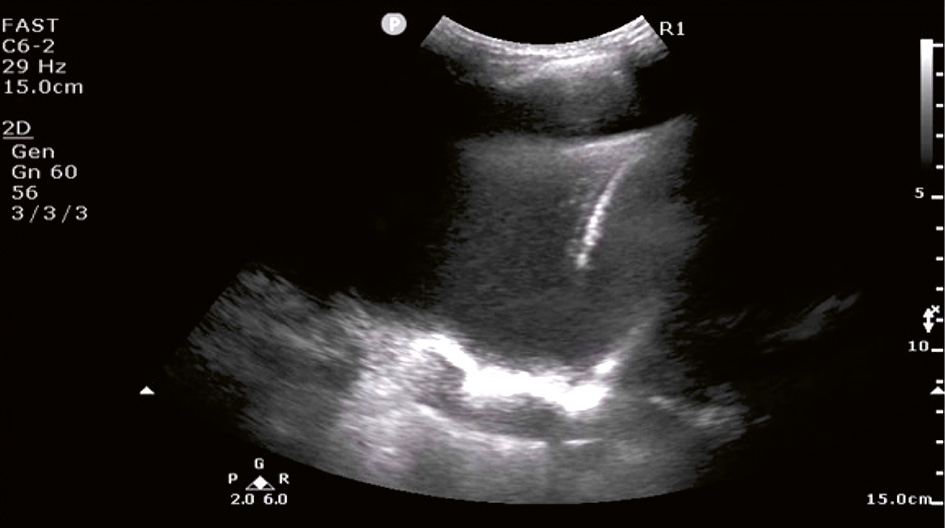

Sonografiskt utseende av pleuravätska (A–D). Pleuravätska identifieras med ultraljud som ett spatium mellan pleura parietale och pleura viscerale [48] och kategoriseras enligt ekogenitet och innehåll [49].

Videoklipp kan hittas på www.lucem.info

A. Anekoisk–homogen svart pleuravätska (1) hos en 65-årig kvinna med hjärtsvikt. I bilden ses kotpelaren på djupet, så kallat »spine sign« (2), och atelektatisk lunga simmande fritt i vätskan, så kallat »jellyfish sign« (3) [50]. Aorta (4) syns också tack vare pleuravätska.

B. Komplex icke-septerad pleuravätska (svart vätska med icke-homogena vita ekon motsvarande fibrin, protein, blod eller var) hos en 19-årig man med icke-infekterad para­pneumonisk pleuravätska. I bilden syns punktformiga fritt flytande ekon (»plankton sign«) [50].

C. Komplex septerad pleuravätska hos en 83-årig man med primär pleurainfektion.

D. Komplex homogen pleuravätska (gråaktig uniform ekogenitet) hos en 37-årig man med empyem. Anekoisk och komplex icke-septerad pleuravätska kan vara exsudat eller transsudat [51-53]. Septerad och komplex homogen pleuravätska har däremot 96 procent positivt prediktivt värde för exsudat [53]. Komplex homogen pleuravätska är oftast empyem eller blod [48].